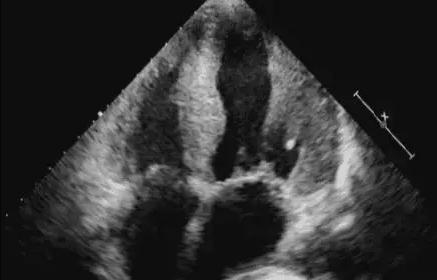

Le principal changement pathologique dans l'hypercardie est l'épaississement de la paroi ventriculaire, qui peut se manifester comme suit :

1. épaississement centripète uniforme du septum interventriculaire et de la paroi du ventricule gauche sans élargissement de la cavité ventriculaire gauche ; ce type est le plus courant ;

2、La cavité cardiaque gauche est élargie, l'épaississement de la paroi ventriculaire n'est pas évident, montrant une hypertrophie excentrique, ce type est le plus souvent accompagné d'une insuffisance cardiaque gauche ;

3) Un épaississement marqué du septum interventriculaire, accompagné d'un épaississement non uniforme de la paroi postérieure du ventricule gauche, doit être distingué de la cardiomyopathie hypertrophique.

Points de diagnostic par ultrasons :

1. une longue histoire d'hypertension ;

2. épaississement uniforme du septum interventriculaire et de la paroi du ventricule gauche ;

3. hypertrophie du cœur gauche ;

4. diminution de l'amplitude du mouvement de la paroi du ventricule gauche ;

5) Insuffisance relative de fermeture de la valve mitrale.